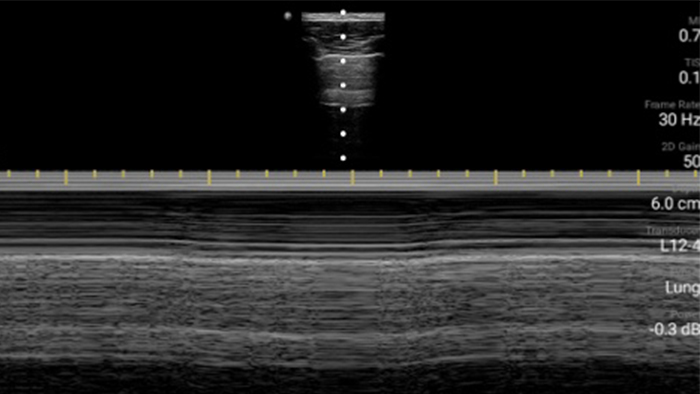

Esté atento a la neumonía por COVID

Lumify puede ayudar a obtener resultados similares a los de una tomografía computarizada de tórax al evaluar la neumonía y el síndrome de dificultad respiratoria en adultos.

• Rango extendido de frecuencias de operación entre 12 y 4 MHz • Tamaño de apertura: 34 mm • 2D, Doppler orientable a color, Modalidad M, XRES avanzado e imágenes armónicas multivariables, SonoCT • Imágenes de alta resolución para aplicaciones superficiales: tejidos blandos, vasculares, superficiales, musculoesqueléticos y pulmonares • Marcador de línea central • Transductor USB-C con cable reemplazable